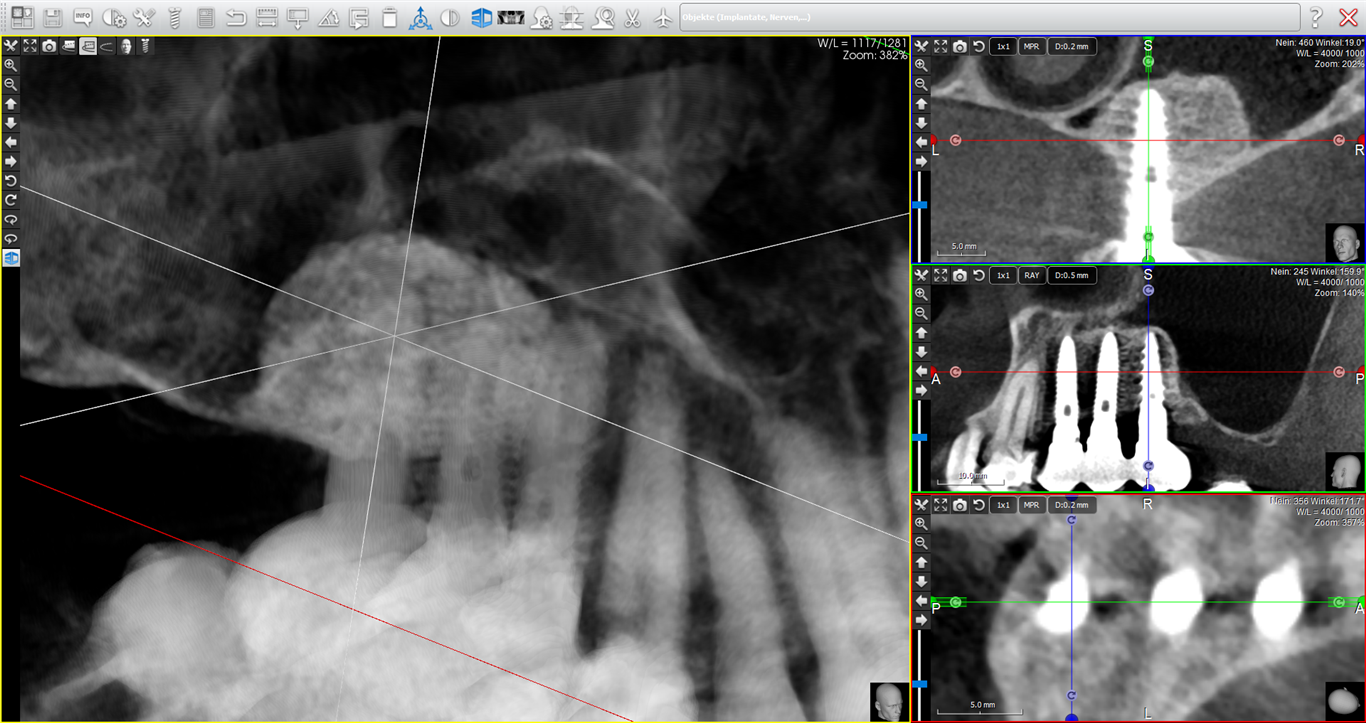

Mit unserem 3-D-Scanner, der die bisher einzigartige Fein-Auflösung von 0,75 Mikrometern bietet, können in allen Bereich der Zahnheilkunde (z.B. Wurzelbehandlungen, Parodontose) und Kiefer- Gesichtschirurgie (Entzündungs-, Nerven- und Nasen-Nebenhöhlendiagnostik) genaue und treffsichere Diagnosen erstellt werden, die dann eine treffsichere Behandlung ermöglichen.

Zehntelmillimetergenaue Kieferknochen-Vermessung und Computer-Operationsplanung für Zahnimplantate und kosmetische Gesichts-Korrekturen

Auf Basis der präzisen dreidimensionalen Abbildung der Kiefer- und Gesichtsknochen sowie der Gesichtsweichteile können Operationen schon im Vorfeld genau geplant und simuliert werden. Wir wissen daher bereits vor der Operation wo z.B. Zahnimplantate gesetzt werden müssen um später Kronen und Brücken in perfekter Kosmetik auf die Implantate aufzementieren zu können und dem Gesicht ein harmonisches Lächeln zu geben. Wenn zu wenig Kieferknochen für Zahnimplantate vorhanden ist, können wir bereits vor der Operation zielgenau eine individuell "maßgeschneiderte" und schonende Operationsmethode auswählen und simulieren um Ihnen in kürzestmöglicher Zeit Ihre prothetischen Wünsche zu erfüllen.

Knochendichtemessung für eine individuelle Prognose der Haltbarkeit von Zahnimplantaten

Je nach dem allgemeinen Gesundheitszustand, einer gesunden Ernährung und einer ausreichenden Vitamin-D-Zufuhr kann sich die Knochenqualität von Mensch zu Mensch stark unterscheiden. Osteoporose ist zwar keine Erkrankung, wie uns Pharmafirmen glauben machen wollen, jedoch hat der "lifestyle" (Bewegungsarmut, ungesunde Ernährung, Vitamin-D-Mangel) einen massgeblichen Einfluss auf die Knochenqualität. Mit der erstmals mit unserem 3-D-Scanner möglichen Messung der Kiefer-Knochendichte kann daher bestimmt werden, ob Zahnimplantate sofort belastet werden können oder ob eine mehrmonatige Einheilzeit notwendig ist um eine langfristige Haltbarkeit der Implantate zu gewährleisten. In seltenen Fällen kann sich auch herausstellen, dass der Kieferknochen gänzlich ungeeignet für Implantate ist und somit kann dem Patienten die Frustration eines Implantatmisserfolges erspart werden.